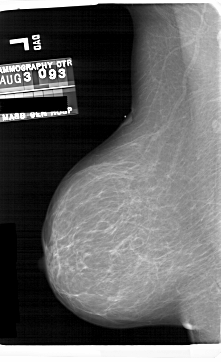

A_1690_1.LEFT_MLO

LEFT_MLO LINES 6871 PIXELS_PER_LINE 4186 BITS_PER_PIXEL 12 RESOLUTION 43.5 NON_OVERLAY